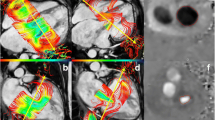

4DF analyses were performed using cloud-based software (Arterys, San Francisco, California, USA). Measurements of aortic and pulmonary artery flow were made at the level of the sinotubular junction for the aorta and midway between the pulmonary valve and pulmonary artery bifurcation, respectively, as per published recommendations [14, 28]. With reference to the 2- and 4-chamber cross-sections, an initial plane was created at end-systole at the mid-leaflet level of the AV valve and orthogonal to flow [16, 27]. Flow was visualized by velocity vectors depicting blood flow directionality in real-time and color-coded for magnitude. Flow through the AV static plane was semi-automatically traced by the software during diastole and manually corrected, as needed. The retrospective valve-tracking AV plane was manually adjusted through diastole to remain near the mid-leaflet level and orthogonal to flow [37], with similar semi-automated tracing of the AV inflow as with the static plane. The regurgitant jet was measured by a plane perpendicular to the jet immediately distal to regions of aliasing, if present [24, 40]. In cases of multiple jets, separate planes were created for each jet and the volume of each jet summed. Care was taken to ensure tracings for each individual jet did not overlap. Time necessary to complete post-processing was recorded for both AIMs and JET.

Our study compares four methodologies calculating regurgitant volume (RVol). Given the clinical utility of regurgitant fraction (RF), we report RF as our outcome. RF was calculated as the quotient of AVVR and AV inflow by the formula RVol/[RVol + semilunar valve net flow (SLNF)]× 100 based on conservation of mass dictating that net inlet and outlet flows are equal. RF was classified as mild (< 30%), moderate (30–39%), moderate-severe (40–49%), or severe (> 50%) [13]. The four methods of calculating RVol were as follows (Figs. 1 and 2; Supplementary videos):

Graphic and mathematical depiction of the indirect methods calculating atrioventricular valve regurgitation (AVVR). a Ventricular stroke volume (SV) is the sum of AVVR and semilunar forward flow (SLFF); b AVVR is derived from the conservation of mass which assumes that atrioventricular net flow (AVNF) equals semilunar net flow (SLNF) in the absence of an intracardiac shunt

Although this is the first such report in children, the JET method by 4DF CMR has been previously found in adults to have high accuracy and reliability relative to the VOL method, particularly in measuring tricuspid regurgitation [40]. 4DF CMR post-processing allows for visualization of flow to aid in the positioning of measurement planes through the use of velocity vectors [37]. Prior work has demonstrated improved accuracy for the AIM method when the atrioventricular plane is placed at the peak inflow velocity as opposed to the valvular plane [37, 50]. The importance of a measurement plane perpendicular to flow likely extends to JET planes and may explain the relatively worse correlation between measurements of mitral RF between the JET and the VOL and AIM methods. Tricuspid regurgitant jets tend to be more central and laminar in orientation as opposed to mitral jets which are more commonly eccentric with a large angle change during systole [40]. In a cohort of 32 children and adults with repaired atrioventricular septal defect (AVSD) and left-sided regurgitation, the regurgitant jets were found to be non-circular, dynamic, and eccentric with a median angulation change of 30–36° during systole [24]. These features increase the technical difficulty of maintaining an orthogonal plane to the mitral regurgitant jet through systole. As can be seen in a subject with repaired AVSD and resultant mitral cleft (Fig. 2b), the large eccentric regurgitant jet which projects along the inferior mural aspect of the left atrium throughout systole complicates creating a true cross-sectional plane. Five of the 18 (28%) subjects in our cohort with mitral regurgitation had a history of AVSD which may have affected accuracy of our JET measurements despite excellent reliability. Our data highlight the clinical applicability of the JET method in pediatric CHD requiring evaluation of tricuspid regurgitation. Although the results were also promising in cases of mitral regurgitation, considerably eccentric or dynamic jets may affect the accuracy of the JET method.